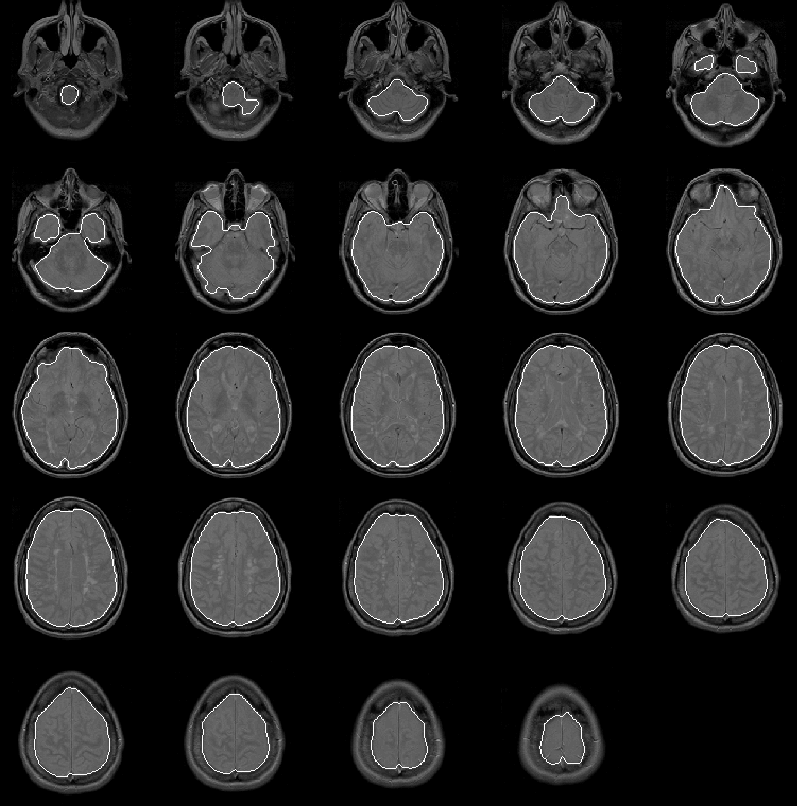

8.4.4 Data Set 4

Figure 8.15 shows the initial brain mask for Data Set 4 overlaid on the PD-weighted scan. As with the previous three data sets, the mask is very good. In slices 11 through 14, the mask extends beyond the intracranial boundary due to the bright areas between the eyes and in the forehead region of the patient. Still, the mask is close enough to the intracranial boundary for the Generate Final Brain Mask process to work effectively.

Figure 8.15: The initial brain mask for MRI Data Set 4 overlaid on the PD-weighted scan.

8.4.5 Data Set 5

The initial brain mask for Data Set 5 is overlaid on the PD-weighted scan in Figure 8.16. The mask is, again, very good. Only a small region of extremely low intensity brain voxels is missed in the lower left corner of slice 2.

Figure 8.16: The initial brain mask for MRI Data Set 5 overlaid on the PD-weighted scan.